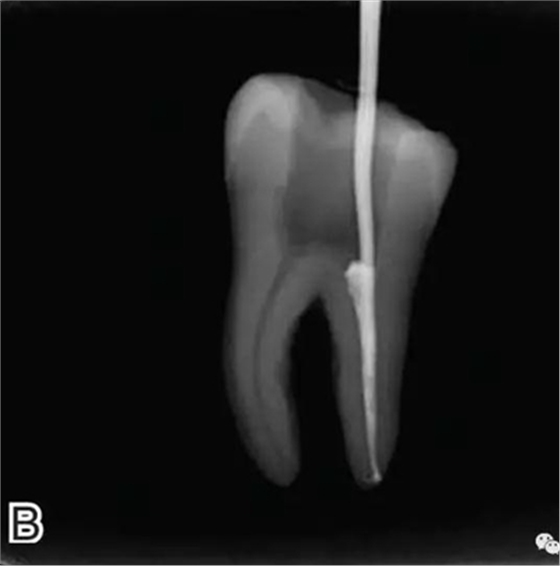

3、試尖

選擇非標(biāo)準(zhǔn)牙膠尖(如0.04、0.06 錐度牙膠尖)作為主尖,型號一般與根管預(yù)備最大號的器械型號一致,能到達(dá)距根尖0.5~1 mm 處,主尖尖段與根管壁緊密接觸。拍試尖X 線片進(jìn)行確認(rèn)(圖3)。

圖3 試尖,A.試主尖 B.拍試尖X片